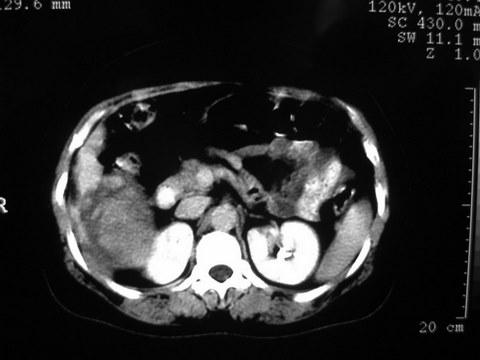

患者 女 51岁 两天前感觉上腹疼,无明显诱因,b超示肝右叶囊实性占位,边缘清楚,其内回声不均匀,ct增强如图,大家看看是什么 ,病人一年前及两月前b超检查只是提示胆囊炎

外院术后,证实肝癌合并出血

增强扫描好像都没有强化的,不管灶周还是灶中心,支持考虑包虫病,别不除外肝囊内内出血,那些一块一块的为血凝块

出病理 中分化肝细胞癌合并出血